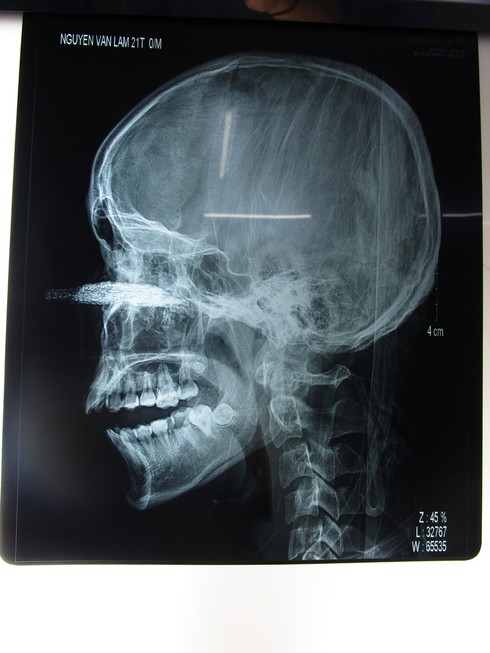

Lưỡi cưa dài 12cm găm vào mắt nam thanh niên 21 tuổi

Hình ảnh qua phim xquang |

Bệnh nhân nhập viện trong tình trạng: tỉnh, tiếp xúc được, có dị vật là 1 phần của lưỡi cưa găm vào giữa mặt ngang gốc mũi và hai mắt.

Sau ca phẫu thuật, bác sĩ lấy được 1 phần lưỡi cưa kích thước khoảng 10x12cm cắm sâu vào xoang hàm trên, có rất nhiều những dị vật nhỏ.